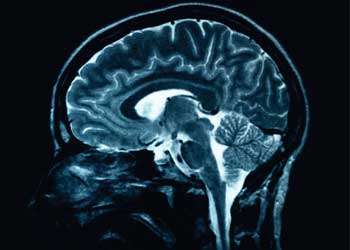

El conferenciante profundizó a continuación en las distintas técnicas de que se están sirviendo los investigadores para avanzar en el conocimiento del cerebro. Entre ellas las llamadas técnicas de neuroimagen, conocidas popularmente como TAC o resonancia.

Las resonancias magnéticas nucleares (RMN), una foto de cualquiera de nuestras partes del cuerpo, pueden decirnos en el caso del cerebro, dónde se han producido alteraciones a medida que envejecemos. Curiosamente, la corteza cerebral, a la que Meana ha calificado como “la parte más humana”, es la que más sufre la degradación del paso del tiempo.

Una evolución de esta misma técnica, la RMN funcional, ha posibilitado conocer qué áreas del cerebro se activan cuando se pide a un sujeto que haga sumas o que piense en una situación triste. Las diferencias de consumo de oxígeno en las distintas regiones del cerebro es la pista que siguen los expertos para hallar las zonas más agitadas.